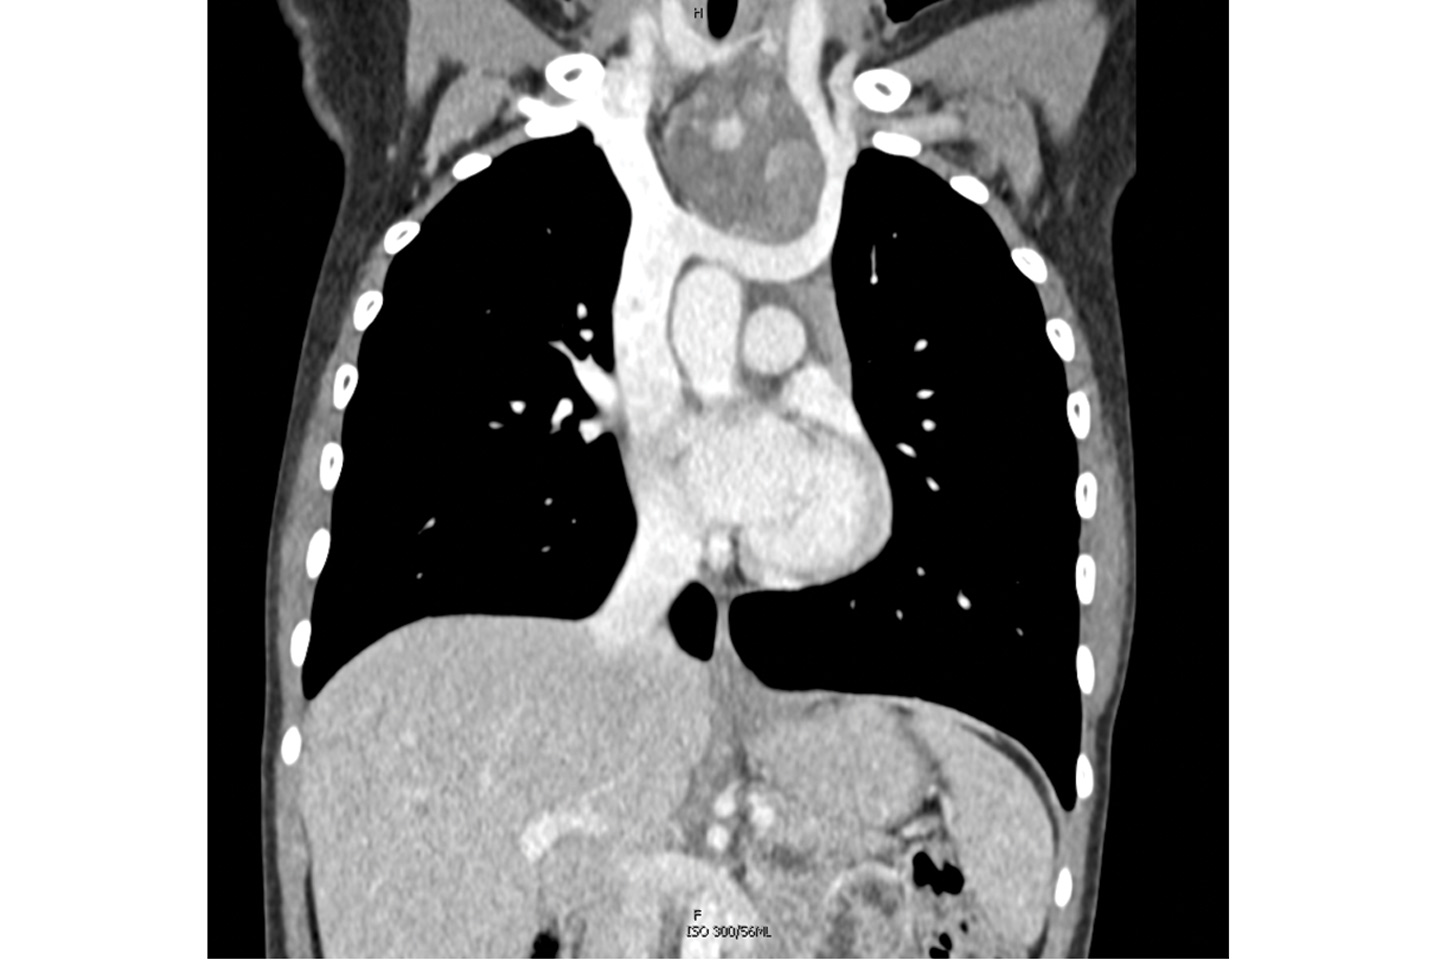

In the spring of 2025, an adolescent female was referred to NYU Langone Health head and neck surgeon Umamaheswar Duvvuri, MD, PhD, for evaluation of an anterior mediastinal mass. The mass was visible by eye, and point-of-care ultrasound revealed it to be a tumor extending from the lower neck into the chest.

A biopsy confirmed a benign teratoma, but resection was expected to be complex; in addition to the tumor’s location spanning the neck and chest, and the concern for thyroid involvement, preoperative imaging revealed it to be in close proximity to the recurrent laryngeal nerve and possibly attached to the brachiocephalic vein.

Preoperative CT scan of the patient’s chest showing the mediastinal tumor. Source: NYU Langone Health.